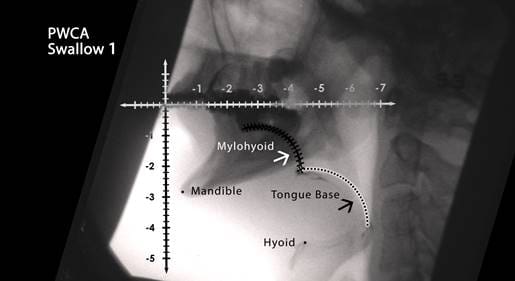

Congenital Aglossia Modified Barium Swallow